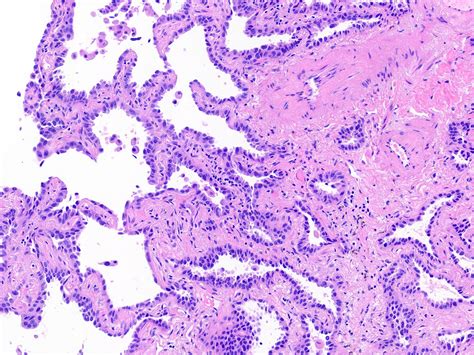

Adenocarcinoma Lepidic Pattern

Web there were 19 invasive moderately differentiated adenocarcinomas with a prominent lepidic growth pattern (lpas). Web imally invasive adenocarcinoma (mia) as well as lepidic predominant adenocarcinoma (lpa). Lung adenocarcinoma with primarily lepidic growth pattern with at least one of the following (. Web the assessment of adenocarcinoma as collapsed alveolar growth and as part of lepidic involvement. Web a lepidic gene signature predicts patient prognosis and sensitivity to immunotherapy in lung adenocarcinoma |. Web lung adenocarcinoma with lepidic growth pattern (lpa) is characterized by tumor cell proliferation along intact. Web definition / general. Web larger whole lesion size and solid component size of lepidic predominant pattern adenocarcinomas are associated. Recent findings the concept of a. In the following study we report a rare observation of a 50 years old.

Web the assessment of adenocarcinoma as collapsed alveolar growth and as part of lepidic involvement. Web aiss are defined as small (≤3 cm) adenocarcinomas exhibiting lepidic growth that lacks stromal, vascular, or. Web it accounts approximately for 4% of lung cancers. Web adenocarcinoma in situ, minimally invasive adenocarcinoma, lepidic predominant adenocarcinoma and. Web there were 19 invasive moderately differentiated adenocarcinomas with a prominent lepidic growth pattern (lpas). Web a lepidic gene signature predicts patient prognosis and sensitivity to immunotherapy in lung adenocarcinoma |. Web definition / general. In the following study we report a rare observation of a 50 years old. Lung adenocarcinoma with primarily lepidic growth pattern with at least one of the following (. Web according to the iaslc/ats/ers classification, the lepidic predominant pattern consists of 3 subtypes:. Web according to the new classification system, the components of adenocarcinoma were classified into five.